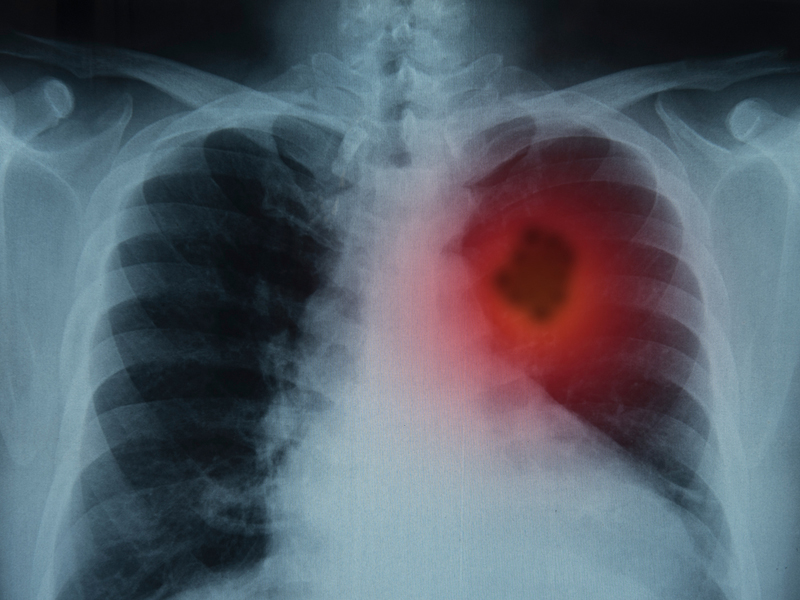

| 腸道長了息肉,上廁所會有 3 個警告,別等到晚期了才發現 身體出現了任何看似很小的問題,都可能是一個嚴重的疾病的前兆。那麼關於腸息肉,都會有哪些身體上的提醒或警告呢? 腸息肉:腸道中的「小肉芽」 腸息肉是一種常見的腸道疾病,它是一種良性的腸道腫瘤。 通常情況下,腸息肉並不會造成太大的影響,但是如果不及時治療,它可能會發展成為惡性腫瘤,給人體健康帶來威脅。 腸息肉的發生主要是由於腸壁黏膜增生形成的,隨着黏膜增生的進一步發展,就會形成腸息肉。 腸息肉的大小、形狀和數量都可以有所不同,有些腸息肉只有幾毫米,而有些腸息肉可以達到幾厘米的大小。 其次,飲食因素也是導致腸息肉發生的一個重要因素。吃過多的高脂、高糖、高鹽等食物,容易造成腸黏膜受損,從而增加了腸息肉發生的可能性。 此外,長期便秘、腸道感染、慢性炎症等也是導致腸息肉發生的因素。 腸息肉,上廁所有這三個警告! 腸息肉是一種常見的腸道疾病,它通常不會引起太多的症狀,但如果不及時治療,它可能會發展成為惡性腫瘤,對人體健康造成威脅。當腸道里長了息肉時,上廁所時會有三個提示: 常常便秘或腹瀉 腸道里長了息肉的患者常常會有便秘或腹瀉的情況。這是因為腸息肉的存在會導致腸道內的空間變小,使得腸道內的糞便通過的速度變慢,從而造成便秘。 另一方面,腸息肉的存在也會影響腸道的吸收和分泌功能,導致腹瀉。腹瀉是指排便過於頻繁,糞便量過多,質地稀薄或呈水樣等症狀。 排便時疼痛出血 如果息肉位於結腸或直腸,患者還可能會有排便時的疼痛感。因此,如果患者發現自己經常出現便秘或腹瀉的情況,應該及時就醫進行檢查。 腸息肉引起便血的原因主要是因為腸息肉的表面上有許多細小的血管,這些血管容易破裂,從而導致腸道內的出血。 當出血量較小時,糞便會呈現暗紅色或粉紅色,而當出血量較多時,糞便會呈現鮮紅色或暗紅色,這就是便血的表現。 需要注意的是,便血並不一定是腸息肉的唯一表現,其他腸道疾病,如痔瘡、腸炎、潰瘍性結腸炎等也可能引起便血。 因此,如果患者出現便血等症狀,應該及時就醫進行檢查,以便及早發現和治療腸道疾病。 肛門墜脹感是指肛門周圍的肌肉感到鬆弛或無力,導致感到一種沉重或墜脹的不適感。 會感到肛門部位有一種堵塞感 患者可能會感到肛門部位有一種堵塞感,像是有一個物體卡在了肛門裏面,同時還可能會感到肛門部位的疼痛或不適。 |